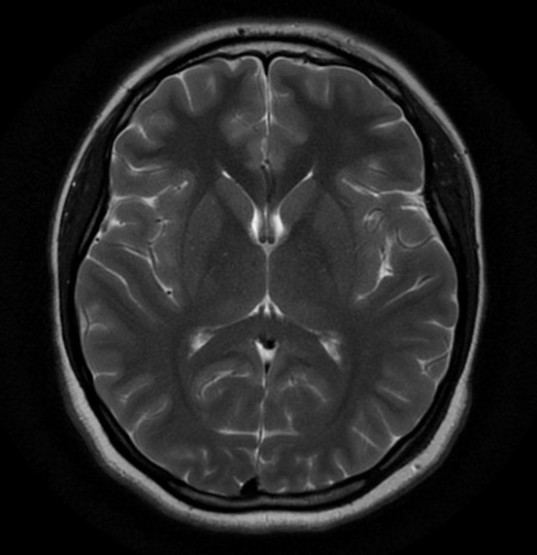

Central CT or MR imaging is not useful in diagnosing GCA however, depending on the clinical situation may be required to rule out other differentials